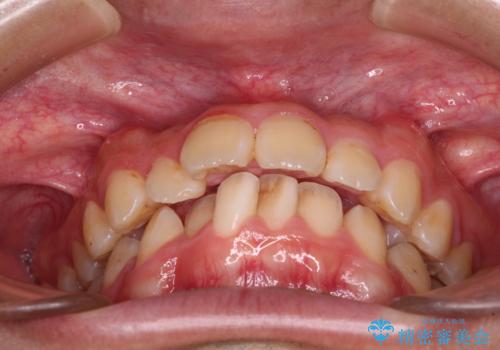

- 深く咬みこんだ前歯と、それに伴い前方に突出した上顎前歯を気にして来院された患者様です。

下顎の歯列は、奥歯が前方に傾斜し、前歯が上顎の歯の付け根に食い込むように内側に傾斜していました。